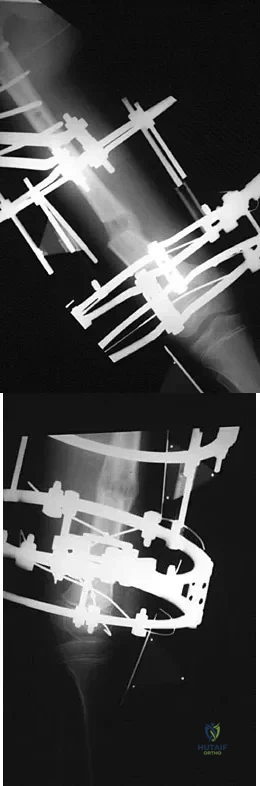

A teenager is undergoing a correction of deformity and lengthening of the femur. Distractions are proceeding as expected; however, during his 6-week follow-up examination, the patient reports that the distraction motors have become harder to turn over for the past 2 to 3 days. Figures 37a and 37b show current radiographs. What is the most likely complication being encountered?

Explanation